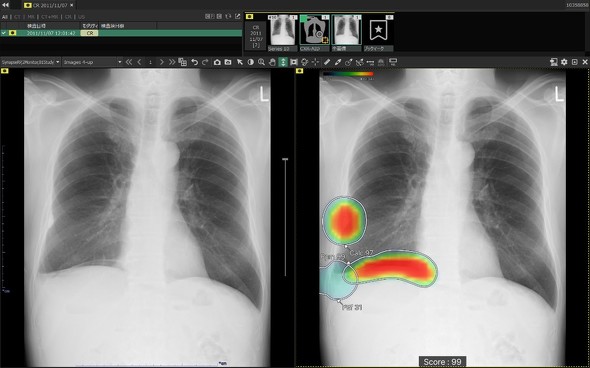

CXR-AIDは、深層学習を設計に用いたAI(人工知能)技術を活用し、胸部単純X線画像から病変が疑われる領域を検出して医師に再確認を促すものだ。これまで、結節と腫瘤影、浸潤影、気胸の3種類の異常所見を検出してきた。

キャプション 左:オリジナル画像、右:解析画像[クリックで拡大] 出所:富士フイルム

新バージョンでは、対象とする異常所見に無気肺、石灰化、瘢痕、胸水、気腹(フリーエア)、心拡大、縦隔拡大の7種類を追加し、計10所見にまで範囲を広げた。これにより、緊張性気胸や消化管穿孔といった、生命予後に関わる緊急性の高い疾患の早期発見を支援する。

表示機能についても改良を加え、異常所見の存在可能性を色付けして示す「ヒートマップ表示」に加え、新たに「輪郭表示」と、これらを組み合わせた併用表示を選択可能にした。モノクロモニターを使用する読影環境においても視認性を確保できる。

また、検出領域ごとに所見名と確信度を示すスコアを個別に表示する機能や、複数の所見が重なる領域でそれぞれの輪郭線を独立して表示する機能を実装し、詳細な画像診断をサポートする。